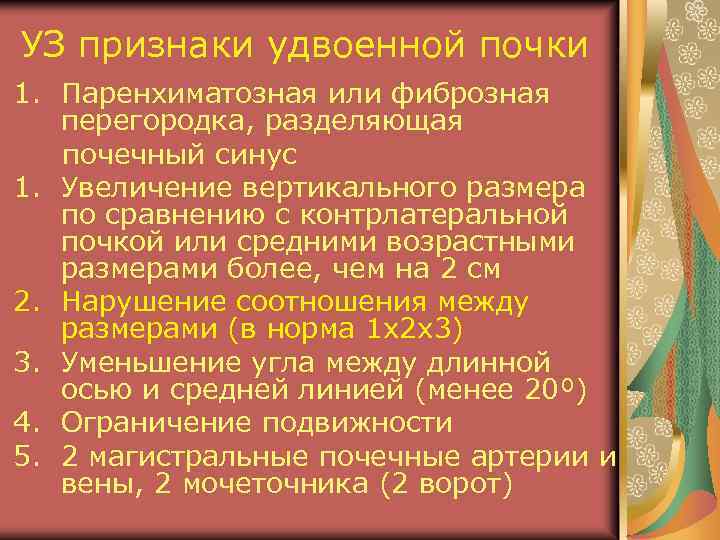

УЗ признаки удвоенной почки 1. Паренхиматозная или фиброзная перегородка, разделяющая почечный синус 1. Увеличение вертикального размера по сравнению с контрлатеральной почкой или средними возрастными размерами более, чем на 2 см 2. Нарушение соотношения между размерами (в норма 1 х2 х3) 3. Уменьшение угла между длинной осью и средней линией (менее 20º) 4. Ограничение подвижности 5. 2 магистральные почечные артерии и вены, 2 мочеточника (2 ворот)

Препарат удвоенной почки 1. Паренхиматозная или фиброзная перегородка, разделяющая почечный синус 2. Увеличение вертикального размера 3. Нарушение соотношения между размерами 4. Уменьшение угла между длинной осью почки и средней линией (менее 20º) 5. 2 ворот с 2 -мя мочеточниками